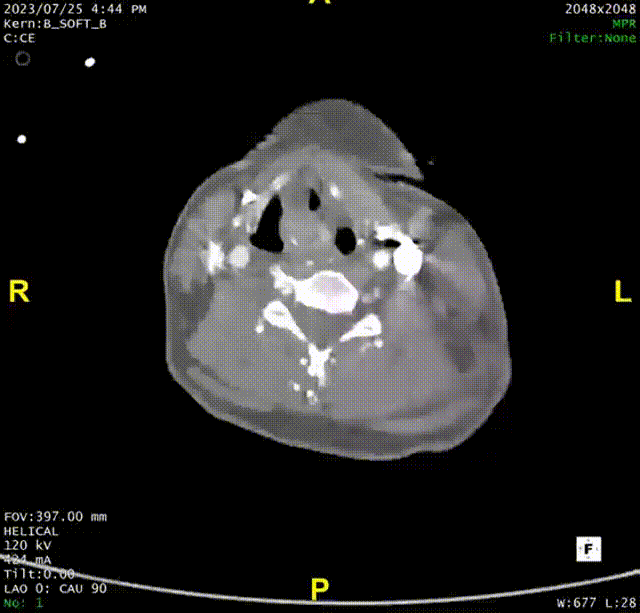

术后随访

术后随访复查造影可见胸主动脉显影良好,假腔血栓化,支架近端无“鸟嘴”,支架内显影良好无内漏。

术后CTA

术后三维重建

术后三维黑白重建